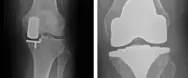

Delprotese vs helprotese

Delprotese (uniknæ) kan anbefales til patienter, der kun har slidgigt i det ene ledkammer - hyppigst på indersiden af knæet. Dette er tilfældet for ca. 30 - 50% af alle patienter med slidgigt i knæet.

Indsættelse af en delprotese i knæet er et mindre indgreb, hvor risikoen for komplikationer såsom infektion og blodpropper er mindre sammenlignet med en total knæprotese.

Sandsynligheden for at opnå et rigtigt godt resultat efter operationen er bedre sammenlignet med totale knæproteser. Bevægeligheden bliver ofte bedre, og chancerne for at kunne ligge på knæ efter operationen er større.